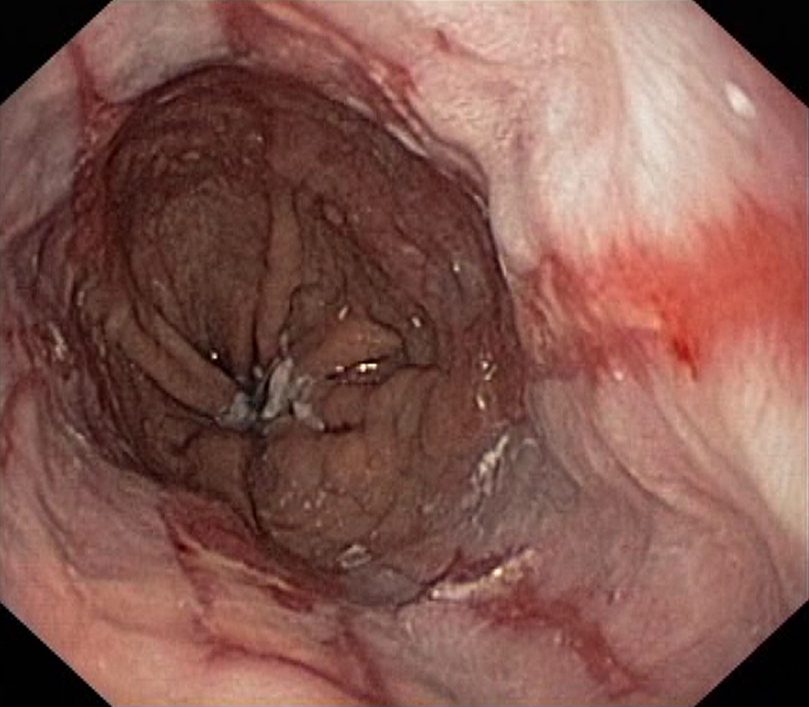

Reflux Oesophagitis Grade D (LA Classification). Just click on a picture!

Reflux Oesophagitis Grade D (LA Classification)